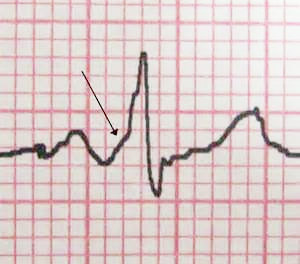

На ЭКГ стрелкой указан характерный признак ВПВ-синдрома – «дельта»-волна в начале желудочкового комплекса

Возбуждение сердца может как замедляться, так и ускоряться. Это связано с работой дополнительных путей передачи импульсов, возникающих при патологии пучков Кента через атриовентрикулярное соединение. В результате возбуждение достигает желудочков быстрее, чем обычно, что приводит к более частым сокращениям. Кроме того, импульсы могут двигаться в обратном направлении к предсердиям, вызывая наджелудочковые тахикардии.